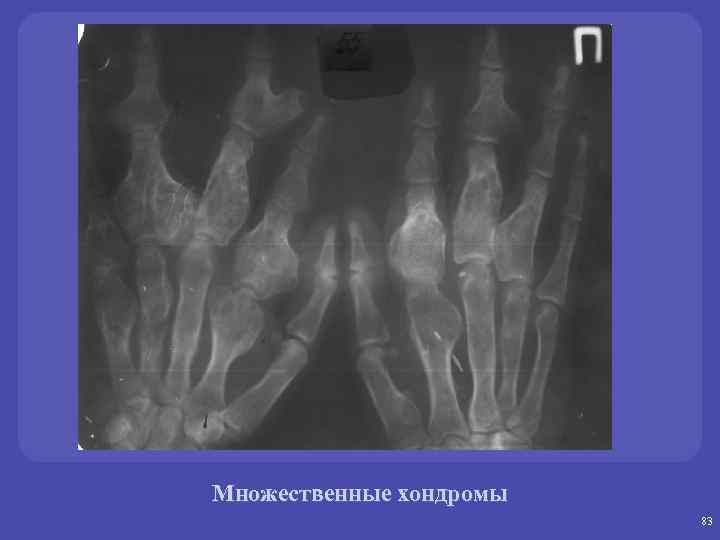

Множественные хондромы 83